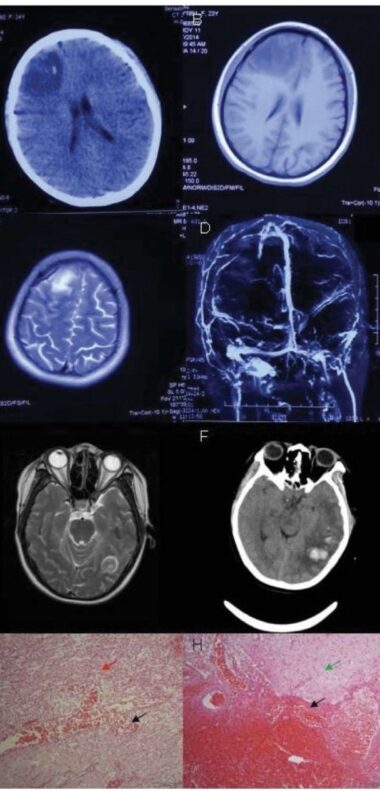

”Post-Thrombotic Complications in Brain Tumor Patients

Patients with brain tumors are at high risk of thrombosis, especially cerebral venous thrombosis (CVT).

Even after successful treatment, post-thrombotic consequences can significantly impact outcomes.

• Venous infarction or hemorrhage